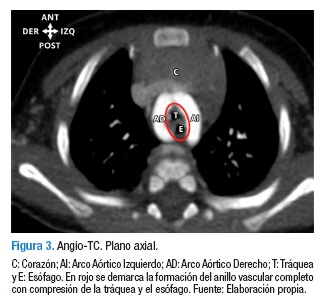

En la Figura 3 se puede observar que el arco izquierdo fue de mayor tamaño que su contra lateral; ambos arcos proveen bilateralmente dos troncos arteriales principales, los dorsales correspondientes a las arterias subclavias y los ventrales a las arterias carótidas comunes, Figuras 4 y 5; dichos vasos se opacificaron adecuadamente con medio de contraste y preservaron su calibre y recorrido normales, sin definirse dilataciones o estenosis patológicas, los dos arcos aórticos generaron morfología en anillo alrededor de la tráquea y el esófago con compresión sobre dichas estructuras. Figuras 1 y 3.

El doble arco aórtico es una malformación cardiovascular congénita poco frecuente, que consiste en la presencia de dos arcos aórticos formando un anillo vascular completo que puede comprimir la tráquea y/o el esófago. En este estudio se presenta el caso de un paciente colombiano, quien ingresó al servicio de urgencias con broncoespasmo y estridor laríngeo, tanto inspiratorio como espiratorio. La angiotomografía computarizada de tórax mostró un doble arco aórtico completo.

The double aortic arch is a rare congenital cardiovascular malformation, in which two aortic arches form a complete vascular ring that can compress the trachea and/or esophagus. The case of a Colombian patient is presented, who arrived to the emergency room with bronchospasm and laryngeal stridor, inspiratory as well as expiratory. The computed tomography angiography showed a complete double aortic arch. In the analysis of this case the epidemiologic, embryonic, genetic, pathophysiologic and clinical review of this malformation is presented. Finally, how the integral analysis from the basics sciences can guide the diagnostic and therapeutic process is shown.

Paciente lactante menor de género masculino y 4 meses de nacido, producto del tercer embarazo de madre de 20 años de edad —grávidas 3, partos 3 (G3P3)— con controles prenatales normales, sin antecedente de exposición a teratógenos conocidos durante el embarazo, con parto institucional sin complicaciones. El paciente ingresó al servicio médico de urgencias con broncoespasmo y estridor laríngeo tanto inspiratorio como espiratorio, pero no presentaba ninguna otra anomalía congénita evidente, razón por la cual no se solicitó estudio cromosómico; a la anamnesis se encontró antecedente de infecciones respiratorias a repetición. Se instauró tratamiento farmacológico para bronquiolitis sin mejoría; por ello, se ordenó una fibrobroncoscopia para descartar una laringomalacia, este examen descartó dicha anomalía y permitió identificar una disminución por compresión extrínseca del lumen de la tráquea en su tercio distal, justo antes de la carina, por esta razón se consideró la posible presencia de un anillo vascular y se realizó una angiotomografía computarizada —angio-TC— de tórax, que evidenció una anomalía congénita de la arteria aorta en anillo vascular completo, con doble arco aórtico, ambos con origen en una arteria aorta ascendente y terminación en una arteria aorta descendente. Figuras 1 y 2.